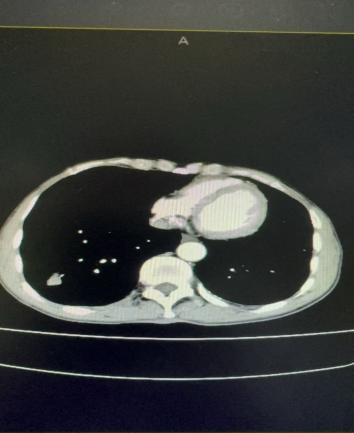

案例一:谭先生,66岁,右肺鳞癌IIIA期。2025年11月18日,在DSA引导及局麻下行经导管支气管动脉栓塞化疗术,术后肿瘤血供明显减少。

栓塞前血供丰富                                                 栓塞后血供明显减少